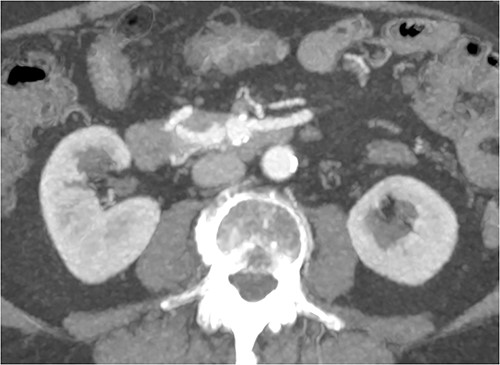

A multiphase CT of the pancreas had unexpected findings. There were no pancreatic masses on the arterial and portal phase study, and no paraaortic or mesenteric lymphadenopathy. The abnormal calcification seen on the previous study corresponded to a dilated vessel along the superior margin of the pancreatic body. This dilated vessel was an abnormal communication between a tortuous ecstatic gastroduodenal artery and the first branch of the SMA, a Buhler’s arc communication. The celiac axis origin was narrowed >90%. No other suspicious solid organ mass lesion was identified. Soft tissues were unremarkable (Figs 5–8).

Multiphase CT pancreas, axial view demonstrating abnormal communication between the CA and the SMA.